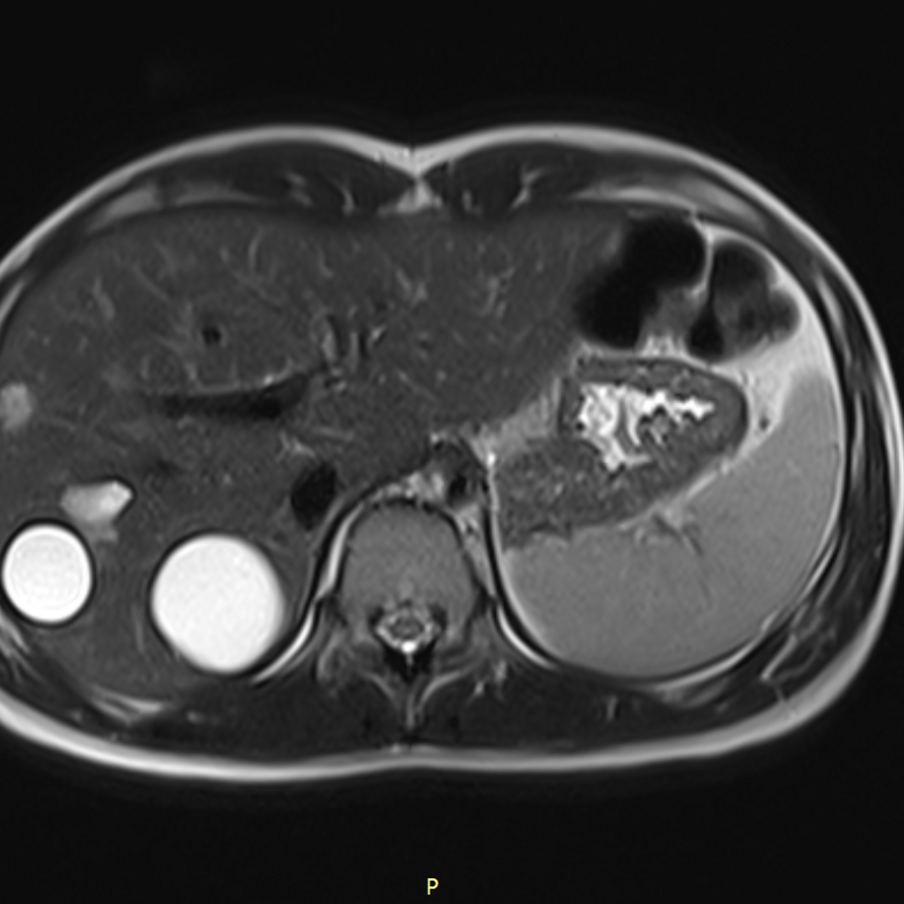

До обращения в столичную клинику ей установили диагноз с помощью компьютерной томографии, а в Москве его подтвердили с помощью МРТ.

– Операцию провели лапароскопически, из печени удалили пять кист. Вначале мы ввели препарат с помощью пункции, который уничтожил личинки, затем удалили содержимое новообразований и извлекли хитиновые оболочки. Диагноз был поставлен на ранней стадии, кисты эхинококка были в диаметре 5 см. И хотя мы встречали гораздо большие – и 10, и 20 см, – сложность была в том, что они располагались в разных местах. При лапароскопической операции результаты гораздо лучше, нет угрозы инфицирования брюшной полости, тем более в таких случаях, когда эхинококковые кисты расположены в разных сегментах.